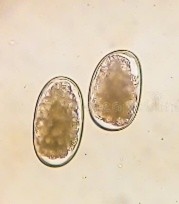

The McMaster technique is a simple quantitative faecal egg count test used to estimate eggs per gram (represented as e.p.g) in a known volume of faecal suspension to the nearest 50 e.p.g. X2 0.15ml of solution is placed into the counting chambers and the sample is examined under a microscope. Systematically, eggs lying within the chambers are counted and an e.p.g result calculated using the following formula;

EPG = total eggs counted in both chambers x50.

This quick method allows us to accurately monitor strongyle type eggs, Nematodirus, tapeworm (to an extent) and coccidia burdens. Some species like Lungworm, encysted tapeworm and Liver Fluke require additional testing and should not use the McMaster technique as a sole means of determining status. To minimise the chance of missing potential eggs, always used a fresh faecal sample, ideally less than 24 hours old. If samples are being pooled, bring in samples from individual animals (with clearly labelled ID). The lab will pool the samples. Refrigerate the sample if there is going to be a delay in getting it to the lab. It is important to point out that if no eggs are seen, it does not guarantee an animal or mob are parasite free, it just means that no eggs were detected in that particular sample. If a result comes back low or negative but an animal is still presenting with symptoms, consult your veterinarian.

Coccidia (oocysts)